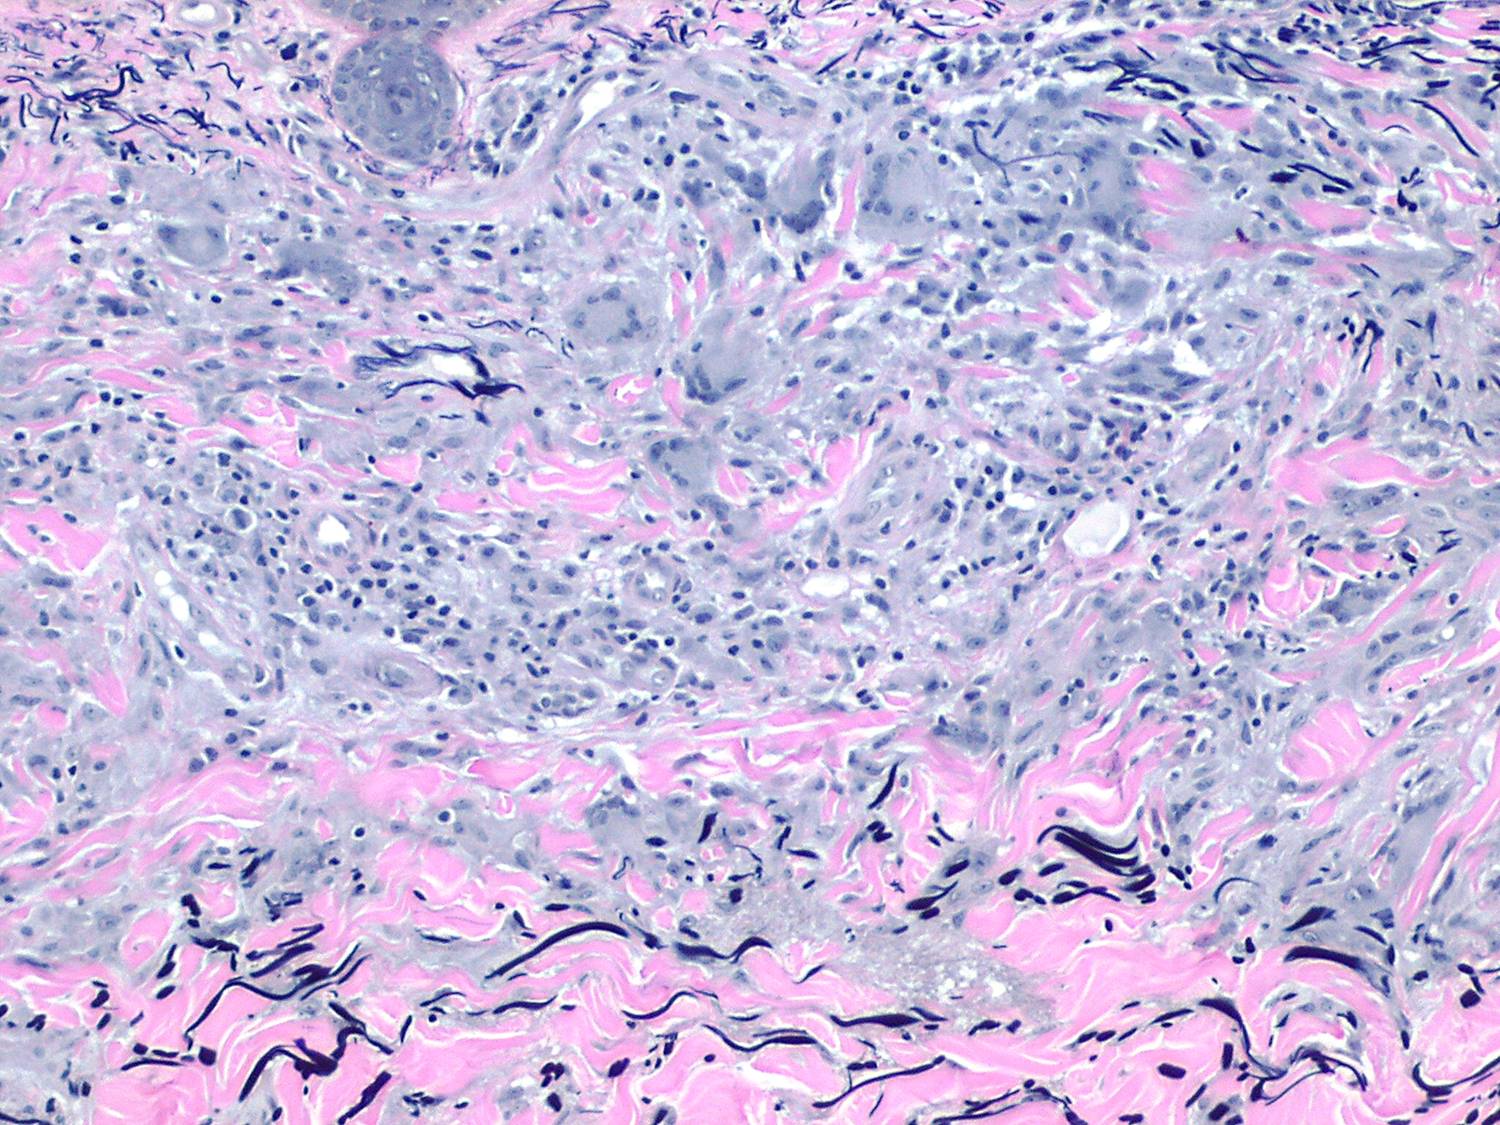

Annular elastic granuloma =الورم الحبيبي الحلقي المرن